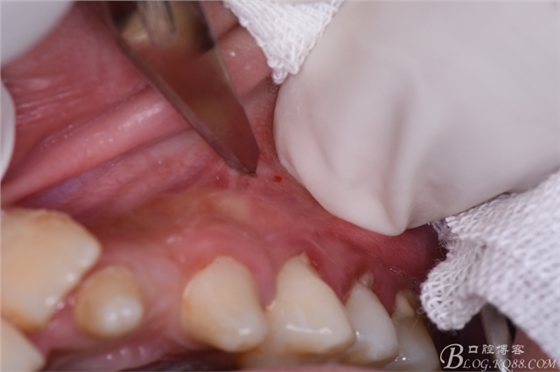

圖7.在24根尖區(qū)的前庭溝黏膜處垂直進(jìn)刀

圖8.做凸面朝向齦方的弧形切口